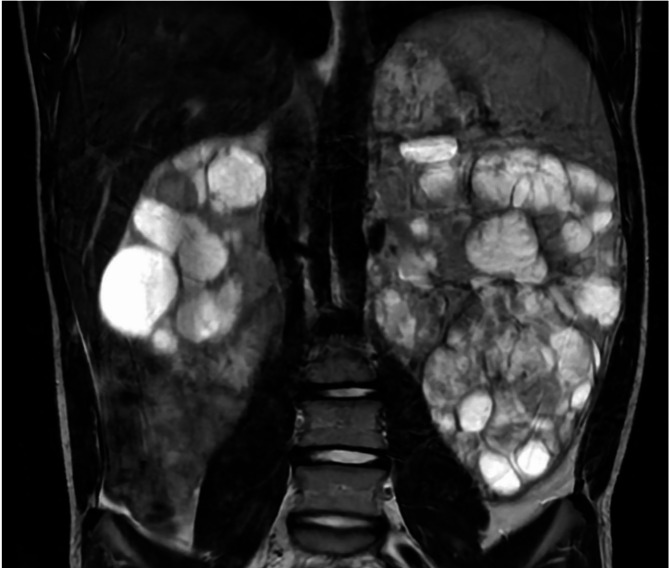

Case presentation: The patient was diagnosed with bilateral polycystic kidneys at 1-year old. At 8-years old he was diagnosed with cutaneous leiomyomas, prompting germline testing which revealed heterozygous variant (c.1301G > A) in the FH gene. Serial imaging identified interval enlargement of several bilateral renal lesions with solid components. Biopsy of a right solid lesion revealed an oncocytic neoplasm. He underwent left total nephrectomy and right partial nephrectomy, revealing numerous bilateral solid and cystic lesions, some with papillary excrescences. Histologic evaluation revealed large cells with eosinophilic to clear cytoplasm and large nuclei with occasional nuclear pseudoinclusions arranged in variable architectural patterns including papillary, tubular, tubulocystic, microcystic and solid. Large cysts were lined by varying thickness of neoplastic cells. By immunohistochemistry, lesional cells were positive for 2-succinocysteine (2SC), TFE3, PAX8 and AMACR, showed retained SDHB, variable FH, and were negative for Cathepsin K, CK20, and CK7. An RNA fusion panel (including TFE3) was negative. Multiple microscopic renal leiomyomas were also present.